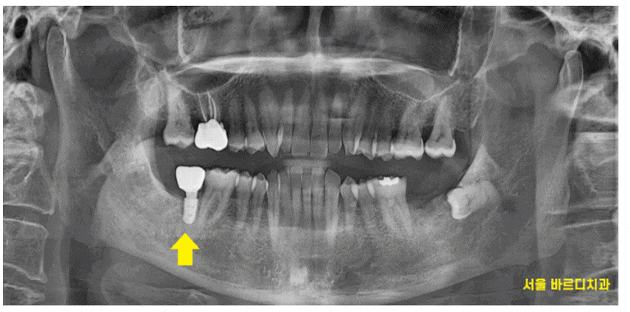

하남시청치과 처음 방문해주셨을 때

왼쪽, 오른쪽 맨 아래 끝에 어금니가

각각 1개씩 상실한 채로 오셨습니다.